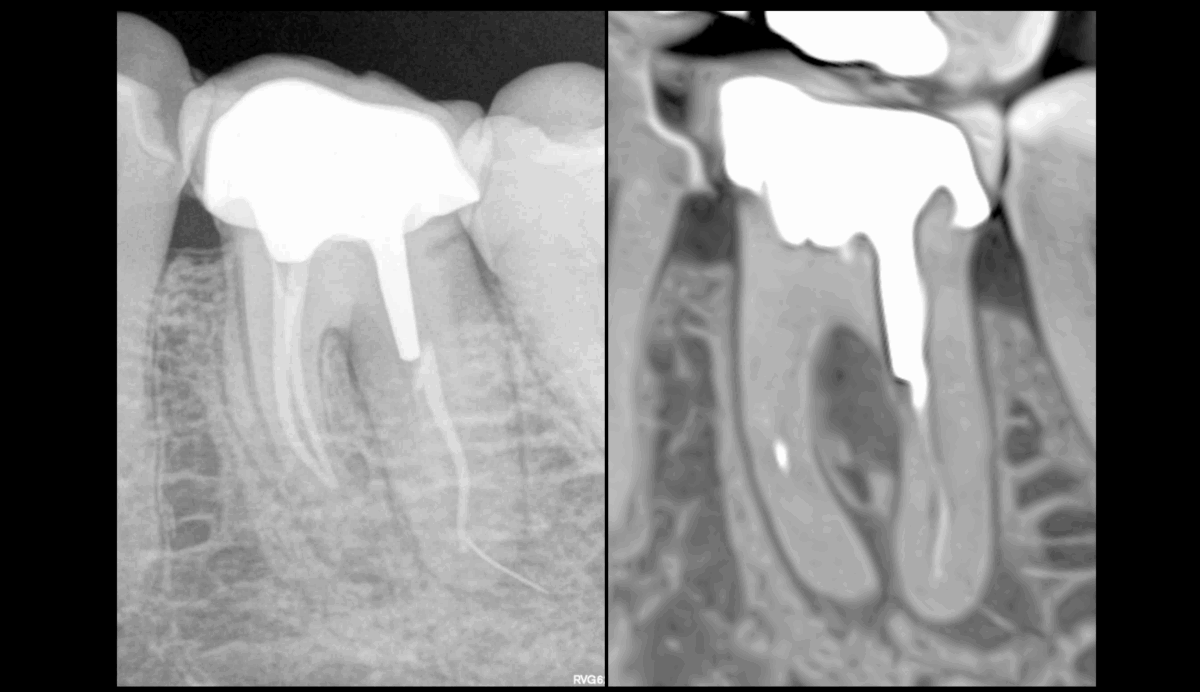

🦷 𝟕 𝐞́𝐥𝐞́𝐦𝐞𝐧𝐭𝐬 𝐚̀ 𝐫𝐞𝐥𝐞𝐯𝐞𝐫 𝐜𝐨𝐧𝐜𝐞𝐫𝐧𝐚𝐧𝐭 𝐜𝐞𝐭𝐭𝐞 𝐝𝐞𝐧𝐭 𝐧°𝟑𝟔 : 𝐥𝐞𝐬𝐪𝐮𝐞𝐥𝐬 ?

🔍 𝐔𝐧𝐞 𝐨𝐛𝐭𝐮𝐫𝐚𝐭𝐢𝐨𝐧 𝐜𝐨𝐮𝐫𝐭𝐞 𝐝𝐚𝐧𝐬 𝐥𝐞𝐬 𝐜𝐚𝐧𝐚𝐮𝐱 𝐦𝐞́𝐬𝐢𝐚𝐮𝐱

🔍 𝐔𝐧 𝟐𝐞 𝐜𝐚𝐧𝐚𝐥 𝐦𝐚𝐧𝐝𝐢𝐛𝐮𝐥𝐚𝐢𝐫𝐞 𝐧𝐨𝐧 𝐭𝐫𝐚𝐢𝐭𝐞́

🔍 𝐔𝐧 𝐢𝐧𝐬𝐭𝐫𝐮𝐦𝐞𝐧𝐭 𝐟𝐫𝐚𝐜𝐭𝐮𝐫𝐞́ 𝐚𝐮–𝐝𝐞𝐥𝐚̀ 𝐝𝐞 𝐥’𝐚𝐩𝐞𝐱 𝐝𝐞 𝐥𝐚 𝐫𝐚𝐜𝐢𝐧𝐞 𝐃

🔍 𝐔𝐧 𝐬𝐭𝐫𝐢𝐩𝐩𝐢𝐧𝐠 𝐝𝐞 𝐥𝐚 𝐫𝐚𝐜𝐢𝐧𝐞 𝐃

🔍 𝐔𝐧𝐞 𝐢𝐦𝐚𝐠𝐞 𝐫𝐚𝐝𝐢𝐨𝐜𝐥𝐚𝐢𝐫𝐞 𝐢𝐧𝐭𝐞𝐫–𝐫𝐚𝐝𝐢𝐜𝐮𝐥𝐚𝐢𝐫𝐞 𝐞𝐧 𝐫𝐞𝐠𝐚𝐫𝐝 𝐝𝐞 𝐜𝐞 𝐬𝐭𝐫𝐢𝐩𝐩𝐢𝐧𝐠

🔍 𝐔𝐧𝐞 𝐥𝐞́𝐬𝐢𝐨𝐧 𝐚𝐩𝐢𝐜𝐚𝐥𝐞 𝐝𝐞 𝐥𝐚 𝐫𝐚𝐜𝐢𝐧𝐞 𝐌

🔍 𝐔𝐧𝐞 𝐥𝐞́𝐬𝐢𝐨𝐧 𝐚𝐩𝐢𝐜𝐚𝐥𝐞 𝐝𝐞 𝐥𝐚 𝐫𝐚𝐜𝐢𝐧𝐞 𝐃